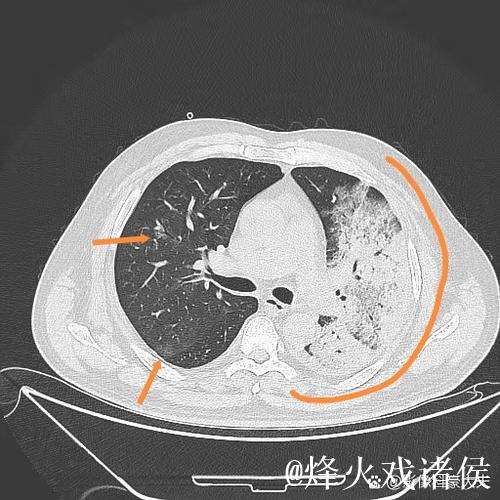

想象这样一个并不夸张的场景某个冬天的深夜,一位普通中年人因为持续高烧、咳嗽不止被家人紧急送往医院急诊。起初他以为只是普通感冒拖一拖就好,但胸闷和呼吸急促让他开始害怕。急诊医生为他安排了血常规、胸部影像检查,很快诊断出是肺炎并且已经出现肺部大片感染。值班的护士迅速为他建立静脉通路,挂上抗感染和补液的药物;呼吸科医生查看片子后,决定将他收入病房,密切监测血氧和生命体征。几天后,随着体温逐渐下降、咳嗽好转,他终于能平稳入睡。出院时,他握着主管医生的手说的一句“谢谢你们救了我”,背后是一整套完备的医疗体系在运转。这种经历,也正是很多人在重病之后才真正理解的现实只有当你真正被送进急诊室,才会明白一个反应迅速、配置合理、运行有序的医疗体系有多重要;只有当你在凌晨三点看到仍在查房的医生和整理病房的护士,才会明白医护人员的责任感远比外界想象更为沉重。